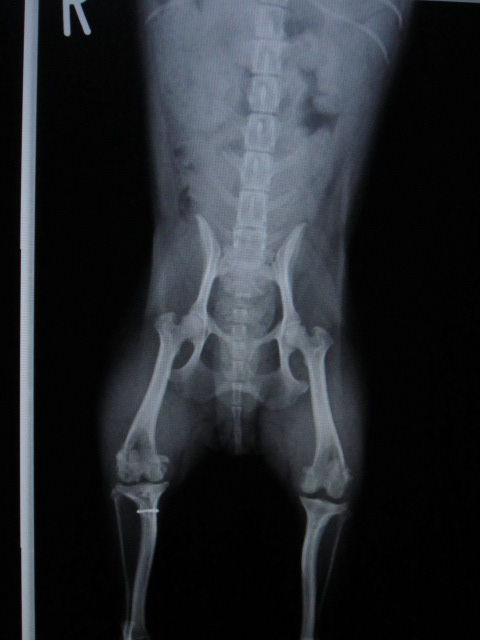

術後のレントゲンです。

右後肢は滑車造溝術と脛骨粗面転移術を行いました。

どちらの足も膝蓋骨がしっかりと大腿骨の滑車の上に乗っています。